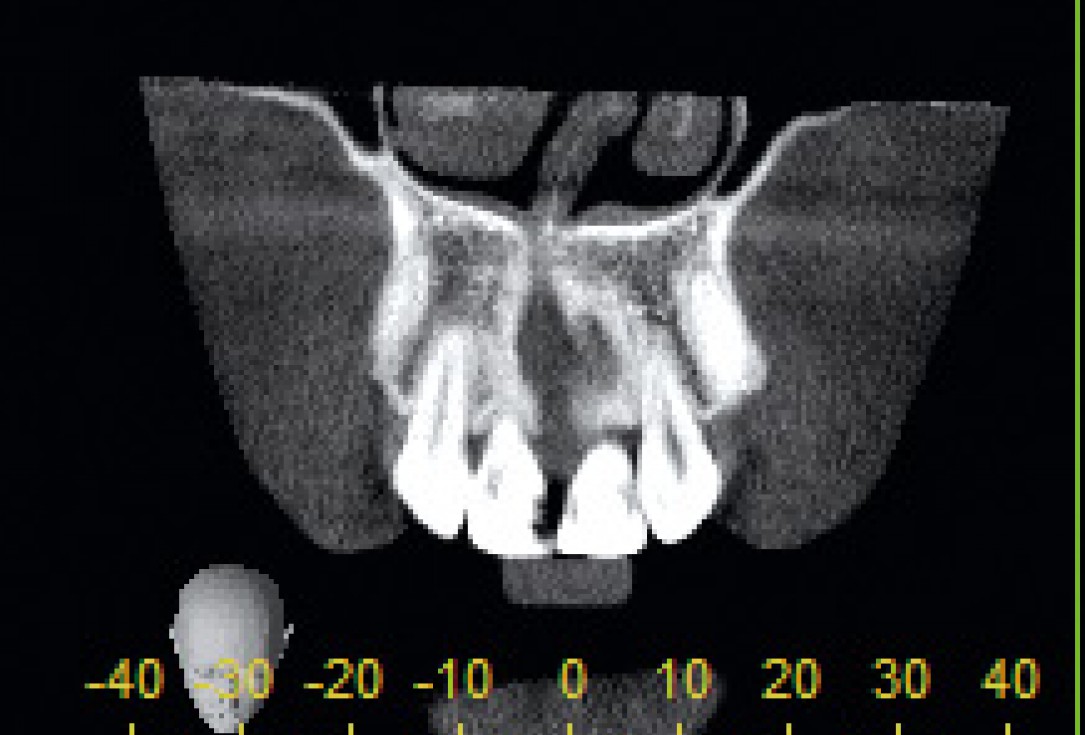

2/26 - CT scan reveals major bone loss in frontal maxillaBone augmentation in aesthetic zone with maxgraft® bonering - Dr. A. Patel